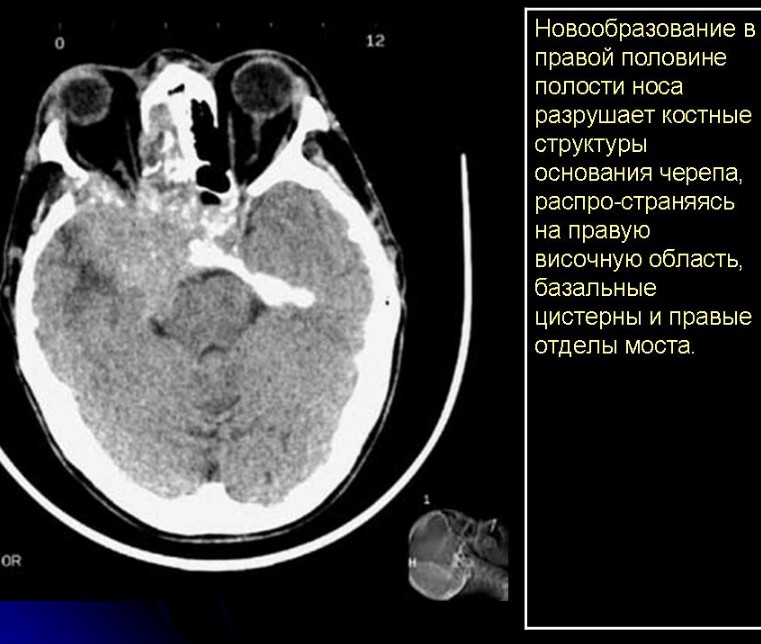

Снимок КТ носа предоставляет исчерпывающую информацию о наличии новообразований доброкачественного и злокачественного характера. Основными признаками опухолевых процессов на  КТ снимке пазух носа является агрессивная костная деструкция, присутствие в мягких тканях патологических образований. Благодаря КТ можно верифицировать  остеомы лобных пазух и другие доброкачественные процессы. Что касается злокачественных опухолей, она чаще исходят из решетчатого лабиринта, гайморовых пазух и полости носа. Лобная и клиновидная пазухи поражаются раком реже. КТ позволяет диагностировать плоскоклеточный, переходно-клеточный рак, аденокарциномы, цилиндромы и другие формы злокачественных процессов.

Отметим, что КТ удается не во всех случаях точно определить распространенность процесса. В частности, сложности вызывает дифференциальная диагностика воспалительных и опухолевых изменений околоносовых пазух при отсутствии деструкции их костных стенок. Эта особенность не только усложняет верификацию самой опухоли, но и не позволяет четко определить границы нарушения. В таком случае проводится контрастное усиление, благодаря которому в артериальную фазу контрастирования, когда происходит выраженное накопление вещества, можно выполнять дифференциацию процессов.

Следует заметить, что в выявлении опухоли гайморовой пазухи важную роль играет КТ-признак деструкции ее задней стенки, что может говорить о распространении нарушения на подвисочную или крылонебную ямки, содержащие сосудистонервный пучок. Поэтому их поражение может быть причиной противопоказаний к операционному вмешательству.